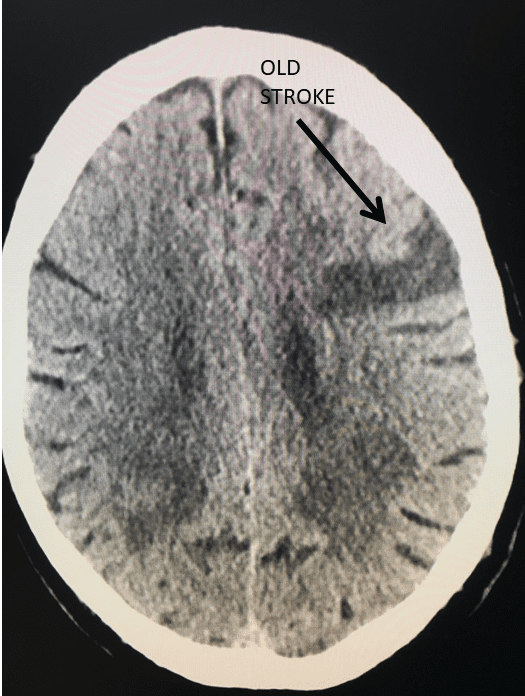

Brain:

Neurosurgeons Collaborate to Treat Giant Symptomatic Meningioma

Author: Ramin Rak M.D., F.A.A.N.S., F.C.N.S., Jonathan L. Brisman M.D., F.A.C.S., Read More!